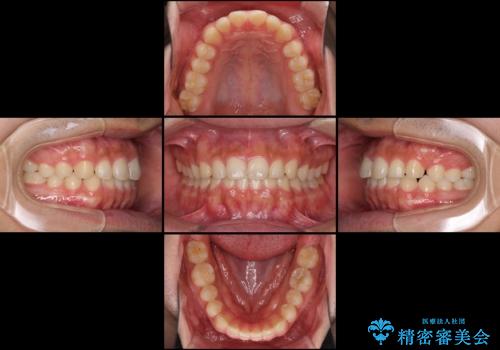

インビザラインによる、すきっ歯の改善

- インビザライン

- 1年5ヶ月

咬合力で上の前歯が前方に押し出されるようにして隙間ができていましたが、矯正治療により全て閉じることができました。

深い咬み合わせも多少改善され、隙間も閉じたことで、前方に出ていた前歯が引っ込んだため、口も閉じやすくなったとのことでした。